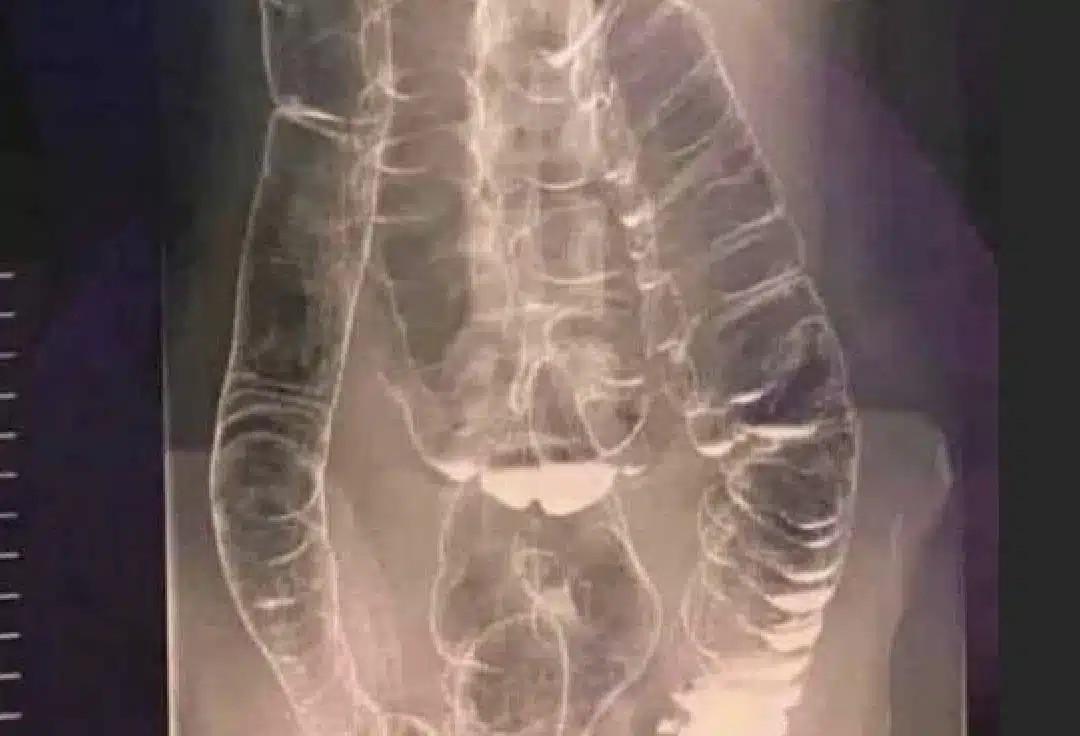

Συγκλονιστική ακτινογραφία ασθενούς με μακροχρόνια δυσκοιλιότητα

Η παρακάτω εικόνα με ακτίνες Χ ανήκει σε μια νεαρή γυναίκα που έπασχε από χρόνια δυσκοιλιότητα για χρόνια. Μια μέρα, η κατάστασή της επιδεινώθηκε και έμεινε για πάνω από δύο εβδομάδες χωρίς κένωση. Αναζήτησε τελικά ιατρική βοήθεια, αλλά τα αποτελέσματα ήταν ανησυχητικά .

Στην ακτινογραφία, μπορείτε να δείτε πώς το κόλον έχει επεκταθεί δραματικά, φτάνοντας μέχρι την περιοχή του θώρακα, κοντά στην καρδιά.

Οι φυσιολογικές πτυχές και διπλώσεις του παχέος εντέρου, που είναι απαραίτητες για τη λειτουργία του, έχουν σχεδόν εξαφανιστεί λόγω υπερβολικού φουσκώματος και διάτασης.